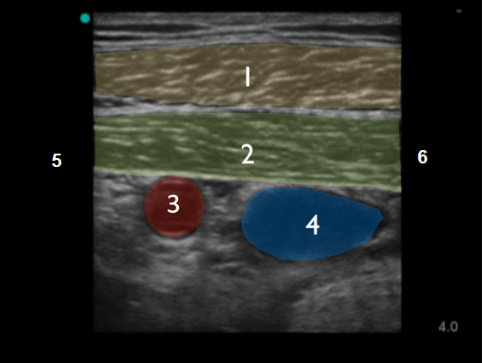

鎖骨超音波テクニック 2画像

小胸筋

腋窩動脈

腋窩静脈

頭蓋骨